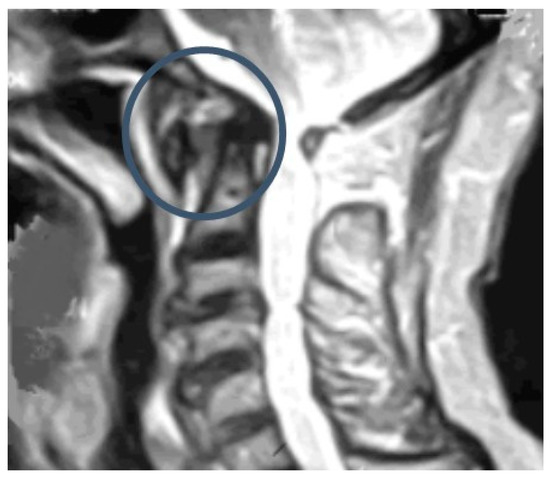

5.3. Magnetic Resonance Imaging (MRI)

6. Treatment